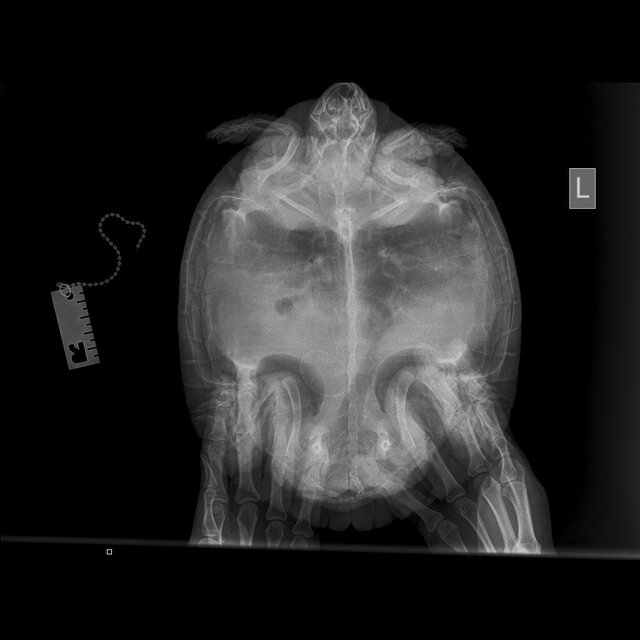

@moth , сделали рентген. Можете по нему что-то сказать?

photo_2023-08-03_20-38-03 (3).jpg

photo_2023-08-03_20-38-03 (2).jpg

photo_2023-08-03_20-38-03.jpg

@MaksimTraper

врач ответила, что возможно отек легких травматического характера и просто капиллярное кровотечение.

В идеале да, сделать кт лёгких, чтобы точно посмотреть. По рентгену криминала нет.